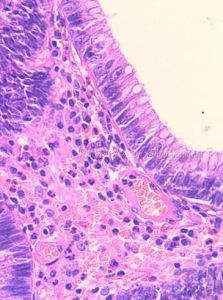

腺瘤是由於腺瘤組織中的腺體分泌物淤積,腺腔逐漸擴張並互相融合成大小不等的囊腔,因而得名。主要見於卵巢,偶見於甲狀腺及胰腺,卵巢囊腺瘤有兩種類型:一種是黏液性囊腺瘤,常為多房性,囊壁光滑,少有乳頭狀增生。另一種是漿液性乳頭狀囊腺瘤,腺上皮向囊腔內呈乳頭狀增生,並分泌漿液,所以稱為漿液性乳頭狀囊腺瘤。

發生於黏膜,呈息肉狀,有蒂與黏膜相連,多見於直腸。其中表面呈乳頭狀或絨毛狀的惡變率較高。結腸多發性腺癌性息肉病常有家族遺傳性,不但癌變率較高,並易早期發生癌變。